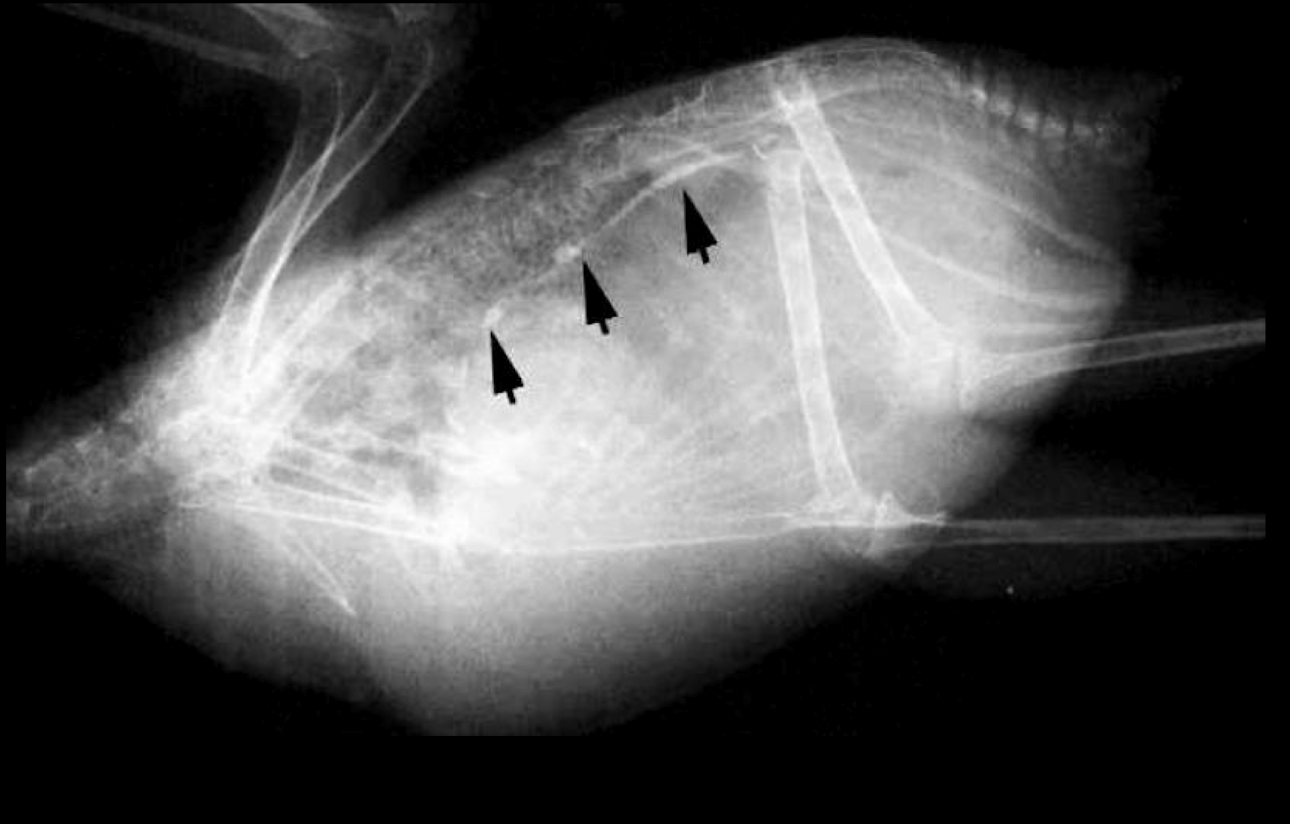

Whats wrong?

pneumonia

Bacterial airsacculitis → thickening of airsac wall

Fungal airsacculitis